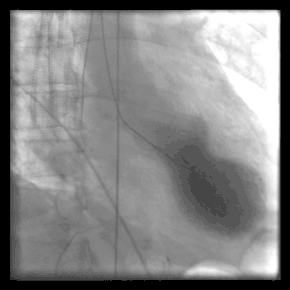

Coronary angiography is a diagnostic procedure that allows visualization of the coronary vessels. Fluoroscopy is used to visualize the lumens of the arteries as a 2-D projection. Should these arteries show narrowing or blockage, then techniques exist to open these arteries. Percutaneous coronary intervention is a blanket term that involves the use of mechanical stents, balloons, etc. to increase blood flow to previously blocked (or occluded) vessels.

Cardiac catheterization often requires the use of fluoroscopy to visualize the path of the catheter as it enters the heart or as it enters the coronary arteries. The coronary arteries are known as "epicardial vessels" as they are located in the epicardium, the outermost layer of the heart.[2] The use of fluoroscopy requires radiopaque contrast, which in rare cases can lead to contrast-induced kidney injury (see Contrast-induced nephropathy). People are constantly exposed to low doses of ionizing radiation during procedures.[3] Ideal table positioning between the x-ray source and receiver, and radiation monitoring via thermoluminescent dosimetry, are two main ways of reducing a person's exposure to radiation.[3] People with certain comorbidities (people who have more than one condition at the same time) have a higher risk of adverse events during the cardiac catheterization procedure.[3] These comorbidity conditions include aortic aneurysm, aortic stenosis, extensive three-vessel coronary artery disease, diabetes, uncontrolled hypertension, obesity, chronic kidney disease, and unstable angina.[4]